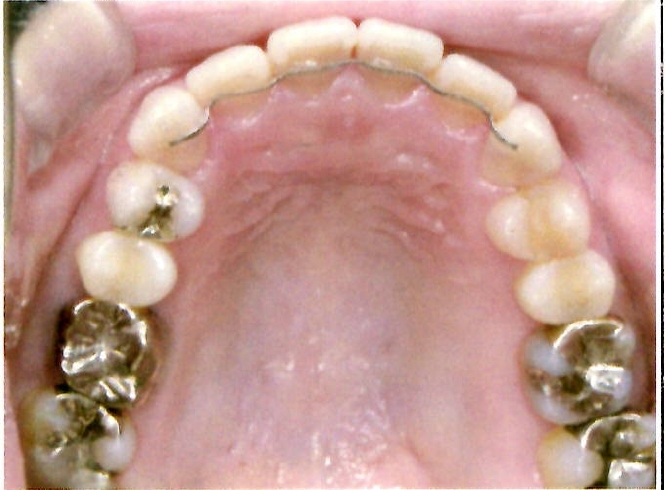

| 主訴・治療前の状態 | 著しい叢生(歯並びのガタガタ)があり、また6歳臼歯(第一大臼歯)が破折していた状態でした。 |

| 治療内容 | 通常の抜歯矯正では第一小臼歯(4番)を抜歯することが多く、その方が治療期間を短縮できますが、小川さんの場合は破折していた6歳臼歯を抜歯し、そのスペースを活用して歯列を整えました。これにより、健康な歯の本数を維持しながら矯正治療を行うことができました。 |

| 治療結果 | 治療前と比較して歯並びが大きく改善し、見た目も大幅に良くなりました。患者様にも大変喜んでいただけた症例です。 |